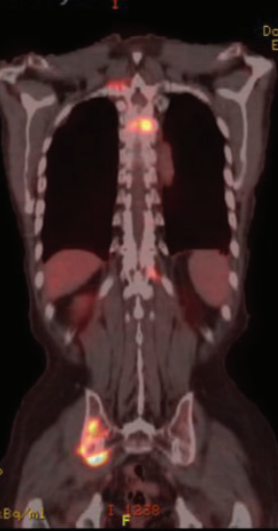

显示右侧腹股沟区域多处淋巴结肿大。患者在接受放疗后定期随访。经过两年的随访,同时进行了胸部影像学检查,结果显示T3椎骨有破坏性/转移性病变。由于同时存在PSA水平升高,因此进行了前列腺MRI并显示左外周前列腺有PI-RADS 5病变。通过前列腺活检确认前列腺腺癌。FDG PET-CT显示在第六肋骨、髂骨和股骨上存在病变(图1)。

图1 患者被诊断为前列腺癌时的FDG PET-CT图像